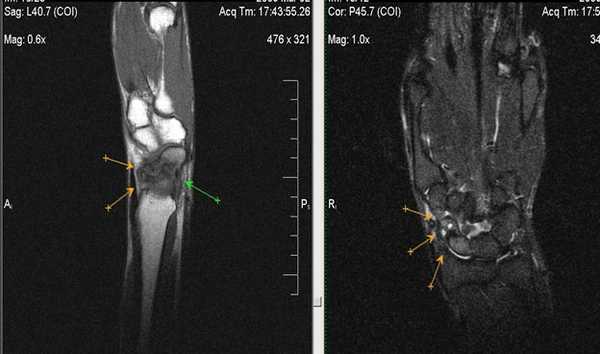

Клинические проявления у пациента: боль и ограничение движений после падения на вытянутую руку 4 месяца назад.

Перелом ладьевидной кости с явлениями асептического некроза проксимального полюса и, связанного с ним, остеоартрита. Ладьевидный перелом обычно происходит из-за падения на вытянутую руку, которое приводит к гиперэкстензии лучезапястного сустава.

Аваскулярный (асептический) некроз нередко сопутствует переломам проксимальной части ладьевидной и переломам полулунной кости, а также неадекватно репонированным и иммобилизированным переломам этих костей. Основная причина - нарушение трофики участка кости при повреждении питающих артерий.

Методом выбора в диагностике и стадировании остеонекроза костей кисти является МРТ.